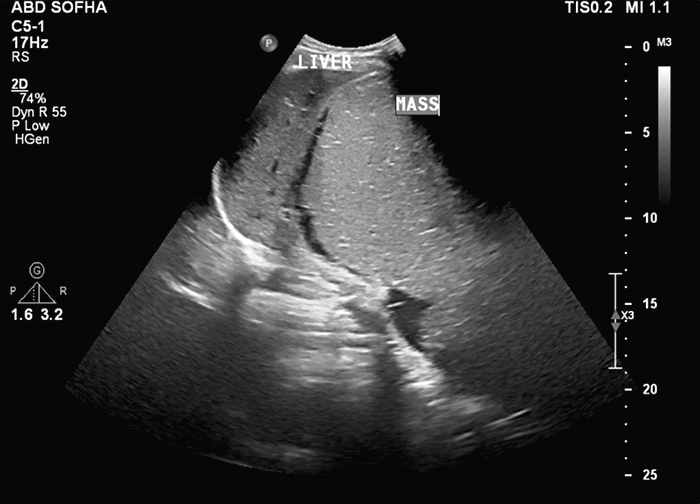

Figure 1. Initial Transabdominal Ultrasound. Published with Permission

Large, well-circumscribed abdominal mass identified on initial obstetrical ultrasound examination

A 33-year-old woman presented after referral to the surgical oncology service at eight weeks gestational age with an incidentally found large abdominal mass on initial obstetrical ultrasound (Figure 1). Magnetic resonance imaging (MRI) of the abdomen identified a 32.5 cm x 28.1 cm x 14.1 cm mass with cystic and solid components, and internal fat, demonstrating significant mass-effect on the liver, gallbladder, inferior vena cava (IVC), bilateral kidneys, and with displacement of intestines from the right hemiabdomen into the left (Figure 2). This was her first pregnancy, and the patient described approximately one year of vague nondescript symptoms including early satiety, constipation, and weight-gain—some of which she had attributed to her pregnancy. Her family history was significant for breast cancer in a paternal aunt. Computed tomography (CT) imaging was performed due to the possibility that this retroperitoneal mass was harboring malignancy as well as for preoperative planning. Imaging showed a large, well-circumscribed 16 x 20 x 30 cm cystic mass containing fluid levels, with a separate 2.4 x 1.0 cm well-circumscribed mass along the celiac axis, without evidence of metastasis or obvious invasion (Figure 3). No specific tumor markers were obtained. Due to concern for malignancy and worsening mass-effect on intraabdominal organs in the setting of viable intrauterine pregnancy, the decision was made to proceed with surgical resection prior to the second trimester.

Less than 40 cases of retroperitoneal tumors diagnosed in pregnancy have been reported in the literature, with only a handful demonstrating mature cystic teratoma.3,5,8 PRMCTs are twice as common in women compared to males and are usually encountered on the left side of the retroperitoneum near the upper pole of the left kidney.3,5,9,10 This differs from our patient, as she presented with a right-sided retroperitoneal tumor. They can be confused clinically with ovarian tumors, renal cysts, adrenal tumors, retroperitoneal fibromas, sarcomas, hemangiomas, and enlarged lymph nodes.10 Most are discovered incidentally on routine ultrasound or on imaging for other indications, as most present asymptomatically, which is consistent with the discovery of this patient's mass on routine obstetrical ultrasound (Figure 1).3,5,7,8 Patients can also present with compressive mass effect symptoms as the masses grow larger, which likely accounts for the nonspecific complaints that our patient described of over one year, with many attributed to pregnancy.5

Ultrasound is often the initial modality used in diagnosis, as it can be used to differentiate between solid and cystic components and may be able to detect calcification from teeth and/or bone, or posterior sound attenuation from sebaceous material and hair within a cyst cavity.4,5 It can be difficult to determine the true location of masses by ultrasound alone, specifically while differentiating between ovarian and retroperitoneal tumors.10 Further imaging with computed tomography (CT) or magnetic resonance imaging (MRI) is often needed for diagnosis and to determine potential malignancy.5,8,10 MRI was performed in our patient to initially characterize the mass,  and CT imaging was employed to further evaluate potential malignancy and preoperative planning. Characteristic findings on CT imaging include well-marginated, multilobulated complex masses with both cystic and solid components; and fluid, fat, soft tissue, and bone densities observed in the retroperitoneal space. The presence of hypoattenuating fat within the cyst or calcifications in the cyst wall is highly suggestive of cystic teratoma.5,10 Our patient's CT imaging demonstrated a large 16 x 20 x 30 cm well-circumscribed cystic mass with fluid levels, without internal calcifications or fat density identified, that did not appear to arise from adjacent organs or demonstrate invasion and was concerning for mesenteric lymphangioma per radiology review (Figure 3). The second 2.4 cm x 1.0 cm mass was well-circumscribed and appeared to contain proteinaceous or hemorrhagic material. Absence of mature tissues, sebum, and occurrence in childhood years have been reported to be predictors of malignant change.5 MRI has been used, specifically during pregnancy, to avoid radiation exposure, as these lesions have a high fat content and appear hyperintense on T1-weighted images.5,8 The MRI performed on our patient demonstrated a 32.5 x 28.1 x 14.1 cm arising from or abutting the inferior surface of the liver, with both cystic and solid components with evidence of internal fat, with differential diagnosis considering fibrolamellar hepatocellular carcinoma, hepatic adenoma, giant hemangioma, leiomyosarcoma of the mesentery, or a cystic teratoma per radiology report (Figure 2).